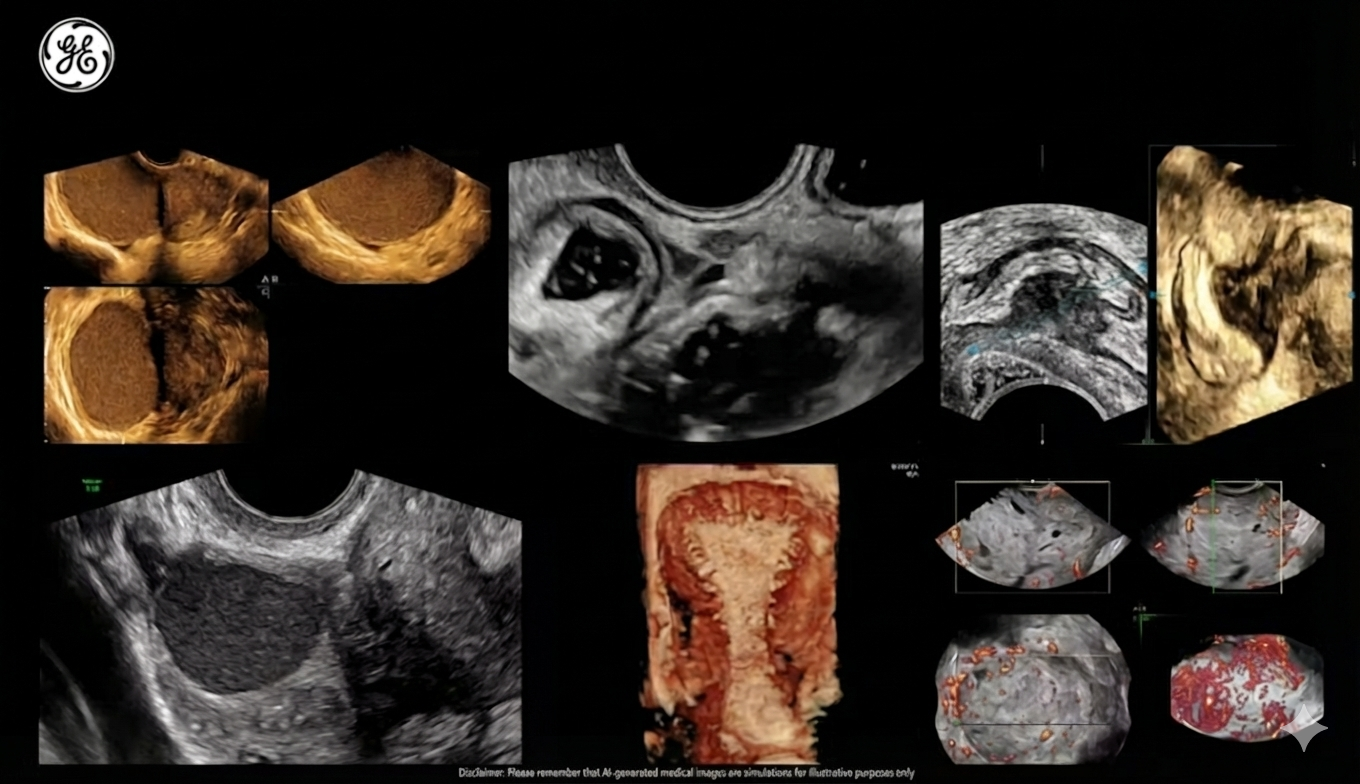

ENDOMETRIOSIS AND ADENOMYOSIS MAPPING SCAN: Advanced Ultrasound for Early and Accurate Diagnosis&Fertility assessment

At our clinic, we utilise state-of-the-art ultrasound technology to offer comprehensive Endometriosis and Adenomyosis Mapping Scans. These advanced scans enable early detection and precise assessment of these conditions, which are often diagnosed late but can significantly impact quality of life.

This non-invasive, high-tech approach ensures a thorough understanding of your pelvic health, guiding personalised treatment strategies to alleviate symptoms and protect overall organ function.

Both endometriosis and adenomyosis frequently cause complex changes within the pelvic region, including chronic inflammation, muscle tension, nerve injuries, and impaired motor functions. The pelvis is an intricate structure composed of muscles, ligaments, nerves, blood vessels, and organs. Damage or alterations to any part can trigger a cascade of issues affecting overall pelvic health.

• Pelvic region mapping scan — a critical element providing detailed insights into the presence, extent, and severity of endometriosis, adenomyosis, and ureteral involvement (quiet obstructions or compression caused by endometriosis can impair urine flow, potentially leading to kidney damage).

Ultrasound mapping is a detailed scan of pelvic organs using advanced imaging techniques. The goal is to look for possible endometriosis deposits, adhesions, ovarian involvement and other abnormalities.

• Thorough evaluation of uterus, ovaries and surrounding structures

What Can It Reveal?

• Hidden lesions in the pelvis that are not always seen on routine scans

• Endometriomas (ovarian cysts), adhesions and scar tissue

• Conditions that may affect fertility or increase pain

• Structural changes in the uterus or ovaries that influence treatment choices